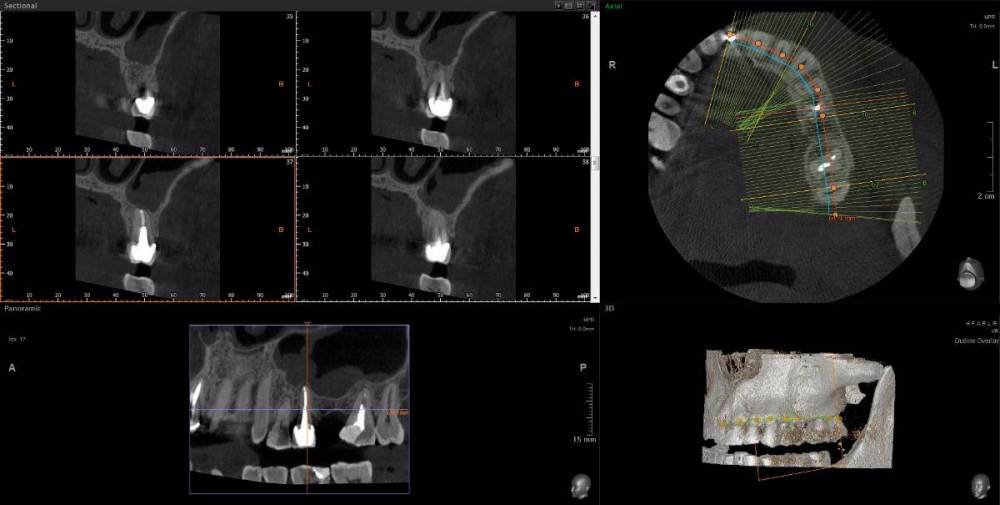

wladdX Опубликовано 15 апреля, 2021 Поделиться Опубликовано 15 апреля, 2021 Несколько скриншотов из вашей КЛКТ. Зуб 25: Зуб 27: Правая сторона: 1 Ссылка на комментарий

red_butler Опубликовано 16 апреля, 2021 Поделиться Опубликовано 16 апреля, 2021 1.5 1.6 перелечивать, 2.4 похоже кариес корня, нужно смотреть очно, 2.5 парадонтологическое поражение, смотреть очно, 2.6 ревизия корневых каналов Ссылка на комментарий